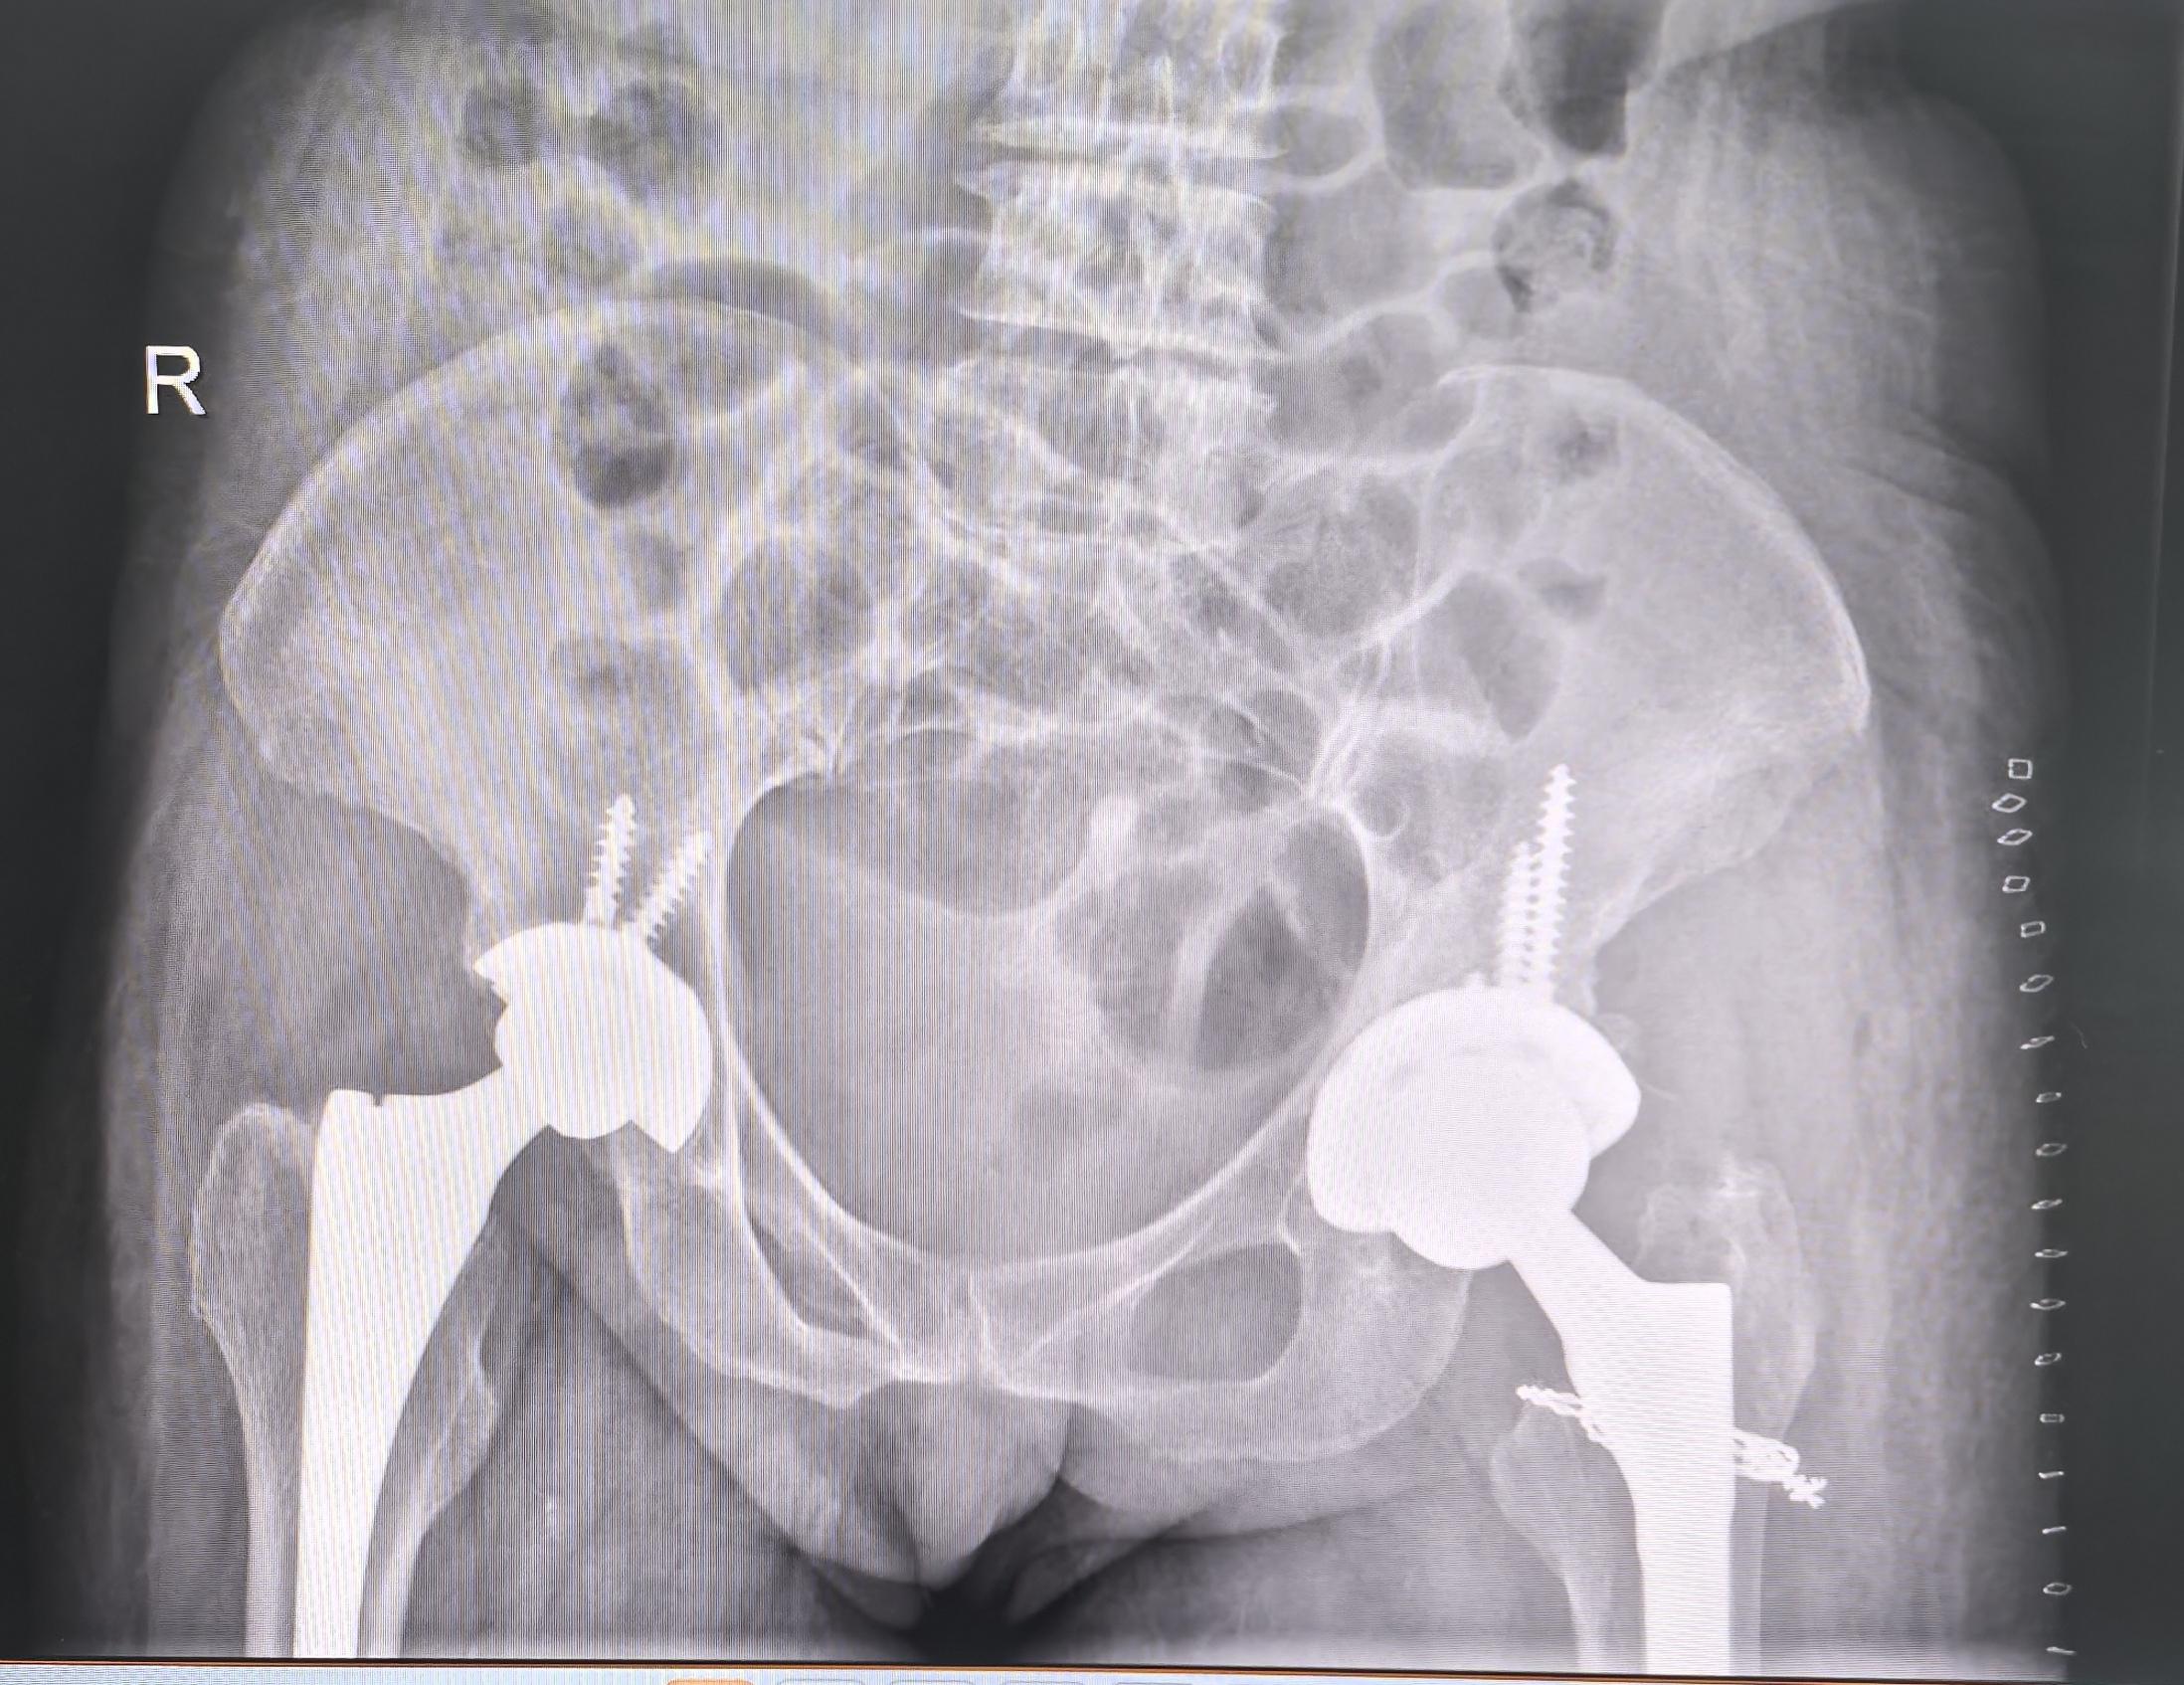

髋关节翻修。髋关节置换术后22年,假体磨损,骨溶解,无菌性松动,翻修术后再次恢复正常生活🌹